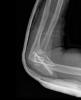

Fractura supracondílea de codo.

Fractura supracondílea de codo.Tras reducción y osteosíntesis.

Fractura supracondílea de codo. Tratamiento con agujas.